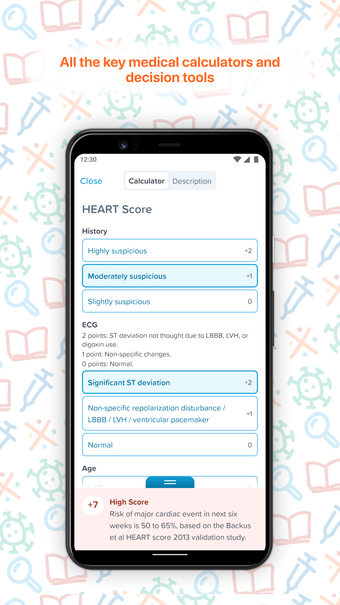

EM:RAP brengt alle beste en meest relevante informatie samen op één plek om het gemakkelijk te maken om klinische vragen te beantwoorden in een noodsituatie of een urgente situatie. Het is een echt uitgebreide, peer-reviewed, klinische bron voor spoedeisende en urgente zorggeneeskunde die u overal, altijd en op elk apparaat kunt gebruiken.